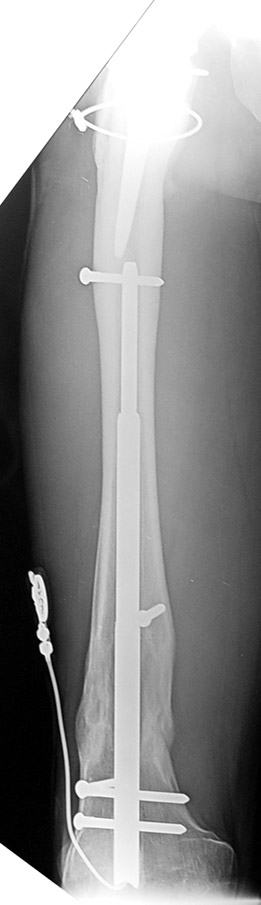

Vaka 2